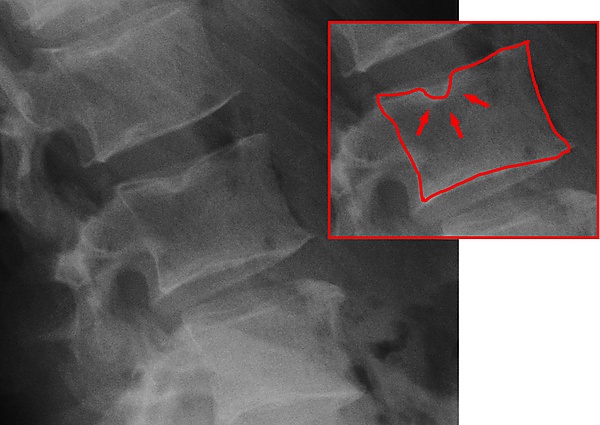

Дегенеративные изменения в межпозвоночных суставах, строго говоря, не считаются остеоартритом, поскольку он поражает только синовиальные суставы, в то время как межпозвоночные суставы являются амфиартродиальными, то есть хрящевыми, допускающими лёгкое или минимальное движение сочленяющихся элементов[9]. Тем не менее, остеоартрит и артрит позвоночника имеют очень похожие проявления, и в биоархеологической литературе их часто объединяют в одну группу. Биоархеологические и клинические исследования показали, что проявление артрита позвоночника связано с такими факторами, как возраст, пол, размер тела, механические нагрузки, осанка двуногого организма и другие[10]. Как и остеоартрит, артрит позвоночника используется в биоархеологических исследованиях для изучения различных аспектов социальных и культурных параметров.

Лесли Грегоричка и Хайме Уллингер из Университета штата Огайо изучили изменения частоты дегенеративных заболеваний позвоночника в шейных позвонках из скелетной коллекции раннего бронзового века (3150 — 2300 гг. до н. э.) из Баб-едх-Дра в Иордании. Цель исследования заключалась в том, чтобы подтвердить или опровергнуть, привело ли увеличение сидячего образа жизни на этой стоянке к снижению рабочей нагрузки. Анализ показал, что частота встречаемости артрита позвоночника снизилась с 21 % до 13 % на протяжении раннего бронзового века на стоянке. Это снижение со временем объясняется уменьшением физической нагрузки на шею в результате изменений, связанных с переносом тяжестей на голове. Далее оба автора предполагают, что полуоседлая группа EB IA (3150-3050 гг. до н. э.), вероятно, занималась мелким садоводством, не оставляя после себя значительных археологических останков; в то время как более поздняя оседлая группа раннего бронзового века II—III (2900—2300 гг. до н. э.) в Баб-едх-Дхра круглый год жила рядом с сельскохозяйственными полями и ручьями, поэтому преодолевала меньшие расстояния для транспортировки урожая и воды[11].